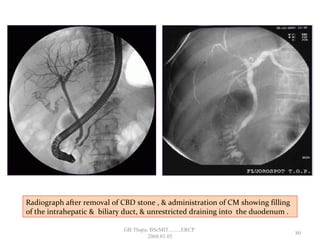

Radiograph after removal of CBD stone , & administration of CM showing filling

of the intrahepatic & biliary duct, & unrestricted draining into the duodenum .

• 75.

Radiograph after removalof CBD stone , & administration of CM showing filling of the intrahepatic & biliary duct, & unrestricted draining into the duodenum . 80 GB Thapa, BScMIT.........ERCP 2068.01.05